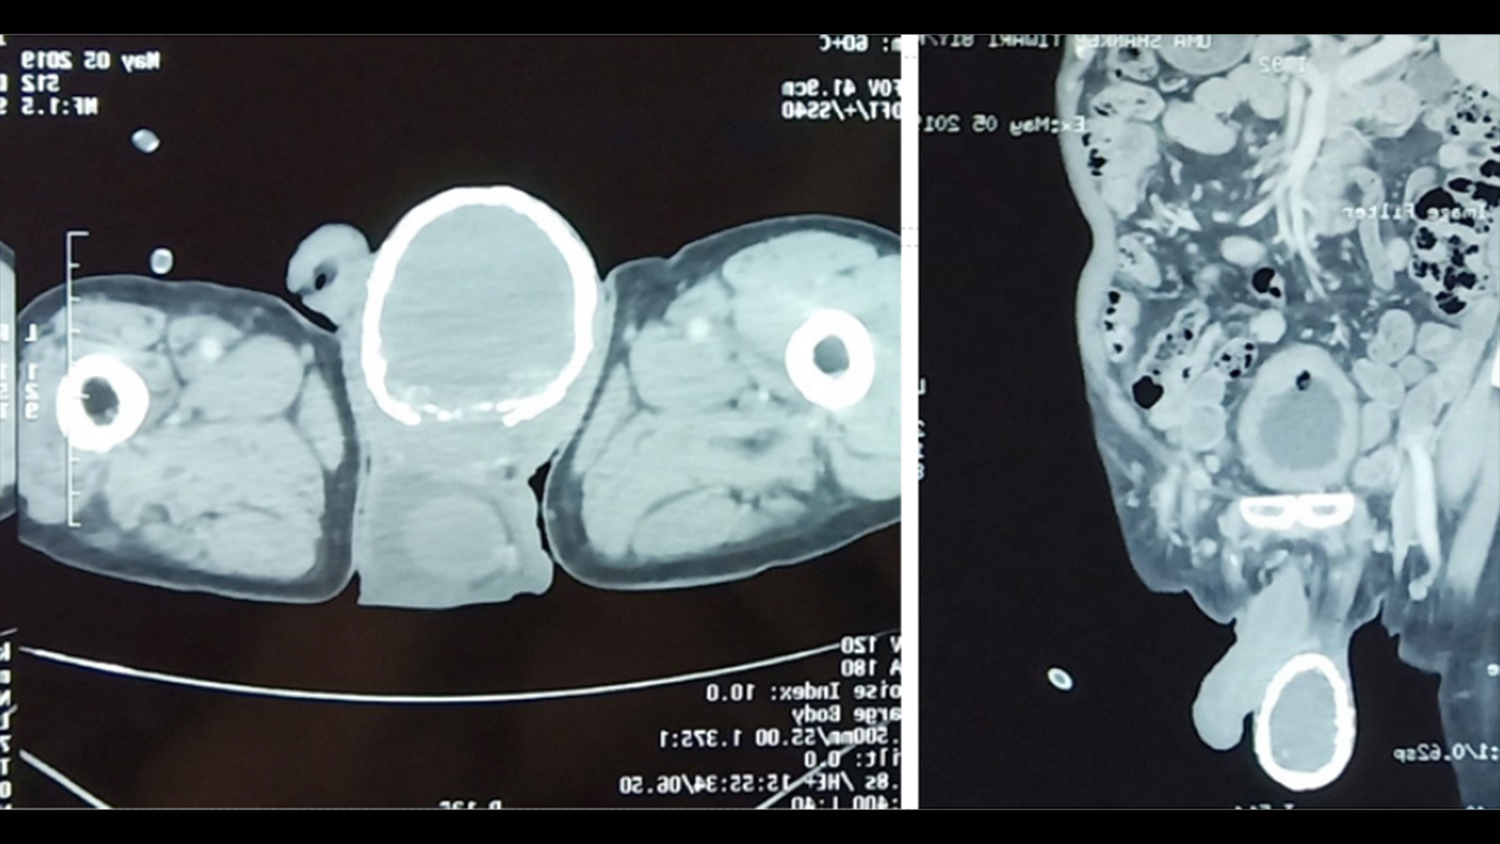

80-летний пациент, обнаружив у себя в моче кровь, поспешил обратиться к врачам. На осмотре те обнаружили еще одну проблему — правое яичко мужчины увеличилось в несколько раз и было твердым как камень. Компьютерная томография показала: у мужчины водянка яичка (гидроцеле). При этом заболевании между оболочками яичек скапливается серозная жидкость. Гидроцеле может быть как врожденным, так и приобретенным, во втором случае оно возникает в результате травм, операций на половых органах, воспалительных заболеваний яичка. Как правило, приобретенная водянка проходит по мере лечения основного заболевания. Возможно и оперативное лечение.

Однако при водянке мошонка остается мягкой, а у пациента она была твердой.

Как оказалось, причина этого — толстый слой кальция, сформировавший внутри своеобразную «скорлупу».

<1>Кальцификация, отложения солей кальция — само по себе нередкое явление. Ее причиной могут стать травмы, операции, почечная недостаточность. В данном случае ее спровоцировала водянка, считают врачи. С таким проявлением кальцификации они столкнулись впервые — впервые подобное отложение кальция было описано в 1935 году и с тех пор известно лишь о нескольких подобных случаях.